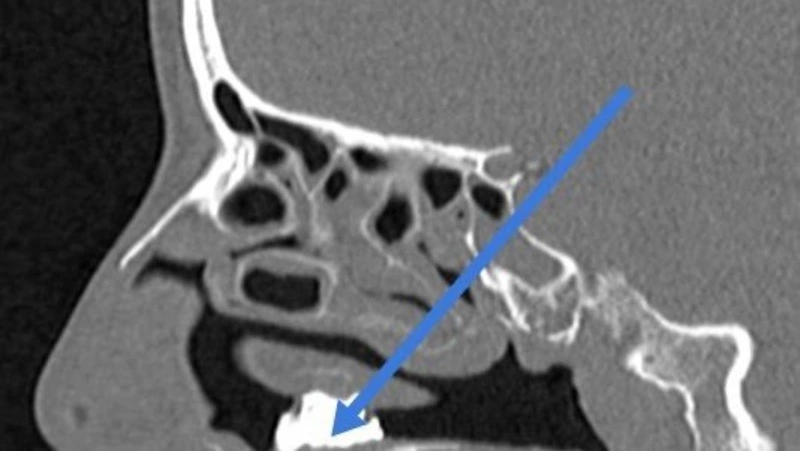

Обследование показало, что в носу у пациентки находится неизвестный инородный предмет. Ее оперативно госпитализировали в стационар.

Во время операции хирурги достали маленькие кусочки угля, которые застряли в грибковых наростах. Каменный или древесный уголь находился в носу у жительницы Подмосковья — врачам определить не удалось. Все вмешательство заняло 40 минут.